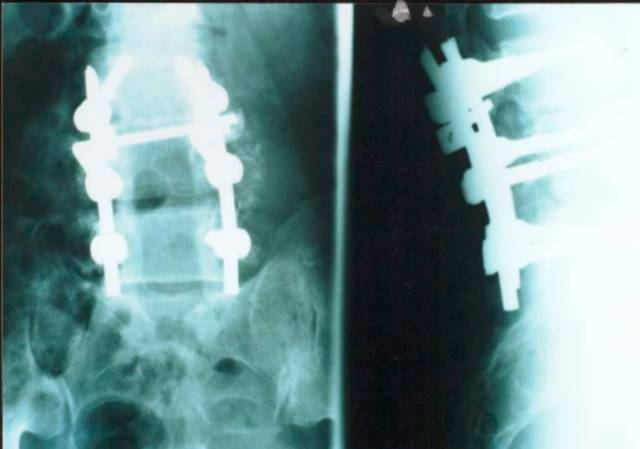

2、原则:(1)腰椎管狭窄症的治疗以手术为主,对椎管及神经根管准确而彻底的减压是治疗成功的关键。(2)术前应明确定位,减压的区域应是引起相应的临床表现的部位,对所有狭窄节段和部位进行充分减压。(3)在彻底解除压迫因素前提下,尽可能的少破坏结构,尽量保持脊柱的稳定性。(4)对于多节段椎管狭窄病人,减压术后对脊柱稳定性影响较大时,应同时作腰椎内固定。(5)腰椎管狭窄合并腰椎不稳的病人,在彻底减压同时亦行腰椎内固定术。(6)术中发现硬膜囊增厚、纤维化等病变时,应切开硬膜,行神经探查、松解术。

3、方法:单纯黄韧带切除术;局限性腰椎管及根管后方减压术;常规腰椎管减压术;腰椎管扩大减压术;腰椎管成形术;腰椎管减压、内固定术。

腰椎管减压内固定术